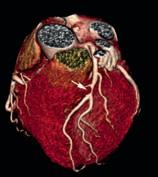

Intrakraniell: Die intrakranielle Gefäßdarstellung ist ein wichtiges diagnostisches Tool in der Therapieplanung und der Behandlung von Gefäßverschlüssen oder Gefäßmissbildungen (Aneurysmen, Angiome). Aktuell stützt sich die Bewertung von intrakraniellen atherosklerotisch-arteriellen Stenosen auf Luminalmessungen mithilfe von DSA, CTA und MRA. Gelegentlich kommt auch der transkranielle Ultraschall (TCD) zum Einsatz. Hierbei stellt die DSA weiterhin den Goldstandard dar. Die MRA wird aufgrund ihrer geringeren Invasivität jedoch wesentlich häufiger eingesetzt. Dabei ist die Timeof-Flight-MRA (TOF-MRA) die am häufigsten verwendete MRATechnik (Abb. 3a), insbesondere zum Ausschluss von Aneurysmen. Bei der intrakraniellen Stenosediagnostik mittels MRA kann infolge von Dephasierungsartefakten der Stenosegrad fälschlicherweise zu hoch eingeschätzt werden. Wegen dieser Einschränkungen hat die TOF-MRA als primäre neurovaskuläre Bildgebungsmodalität an Bedeutung verloren. Außerdem ist ihre räumliche Auflösung im Vergleich zu den anderen MRA-Techniken geringer, sodass die CTA bei der Beurteilung kleinerer Arterienabschnitte der TOF-MRA überlegen ist (Abb. 3b).

Abb. 3a

Abb. 3b

Abbildung 3a, b: Intrakranielle Gefäßdarstellung.

a: Mittels Time-of-Flight-MRA (TOF-MRA) erhobener Normalbefund (Arterien sind hell dargestellt).

b: In der CT-Angiographie zeigt sich ein Verschluss der A. cerebri media rechts.

der Vergangenheit haben jedoch gezeigt, dass es keinen signifikanten Unterschied hinsichtlich der

Genauigkeit der Gefäßdarstellung zwischen CTA und MTA gibt (Literatur beim Verfasser).